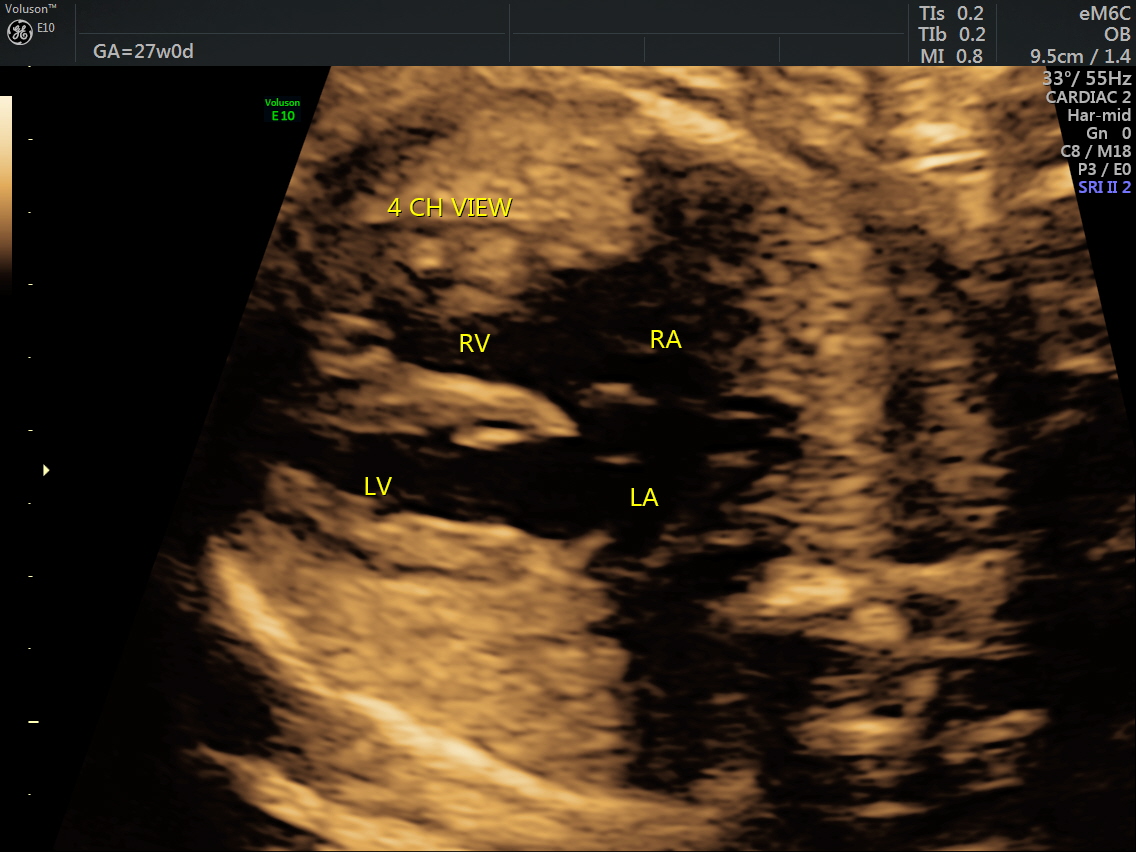

RT AORTIC ARCH_9 Published June 17, 2016 at 1136 × 852 in Rt aortic arch and aberrant left subclavian artery ← Previous Next →